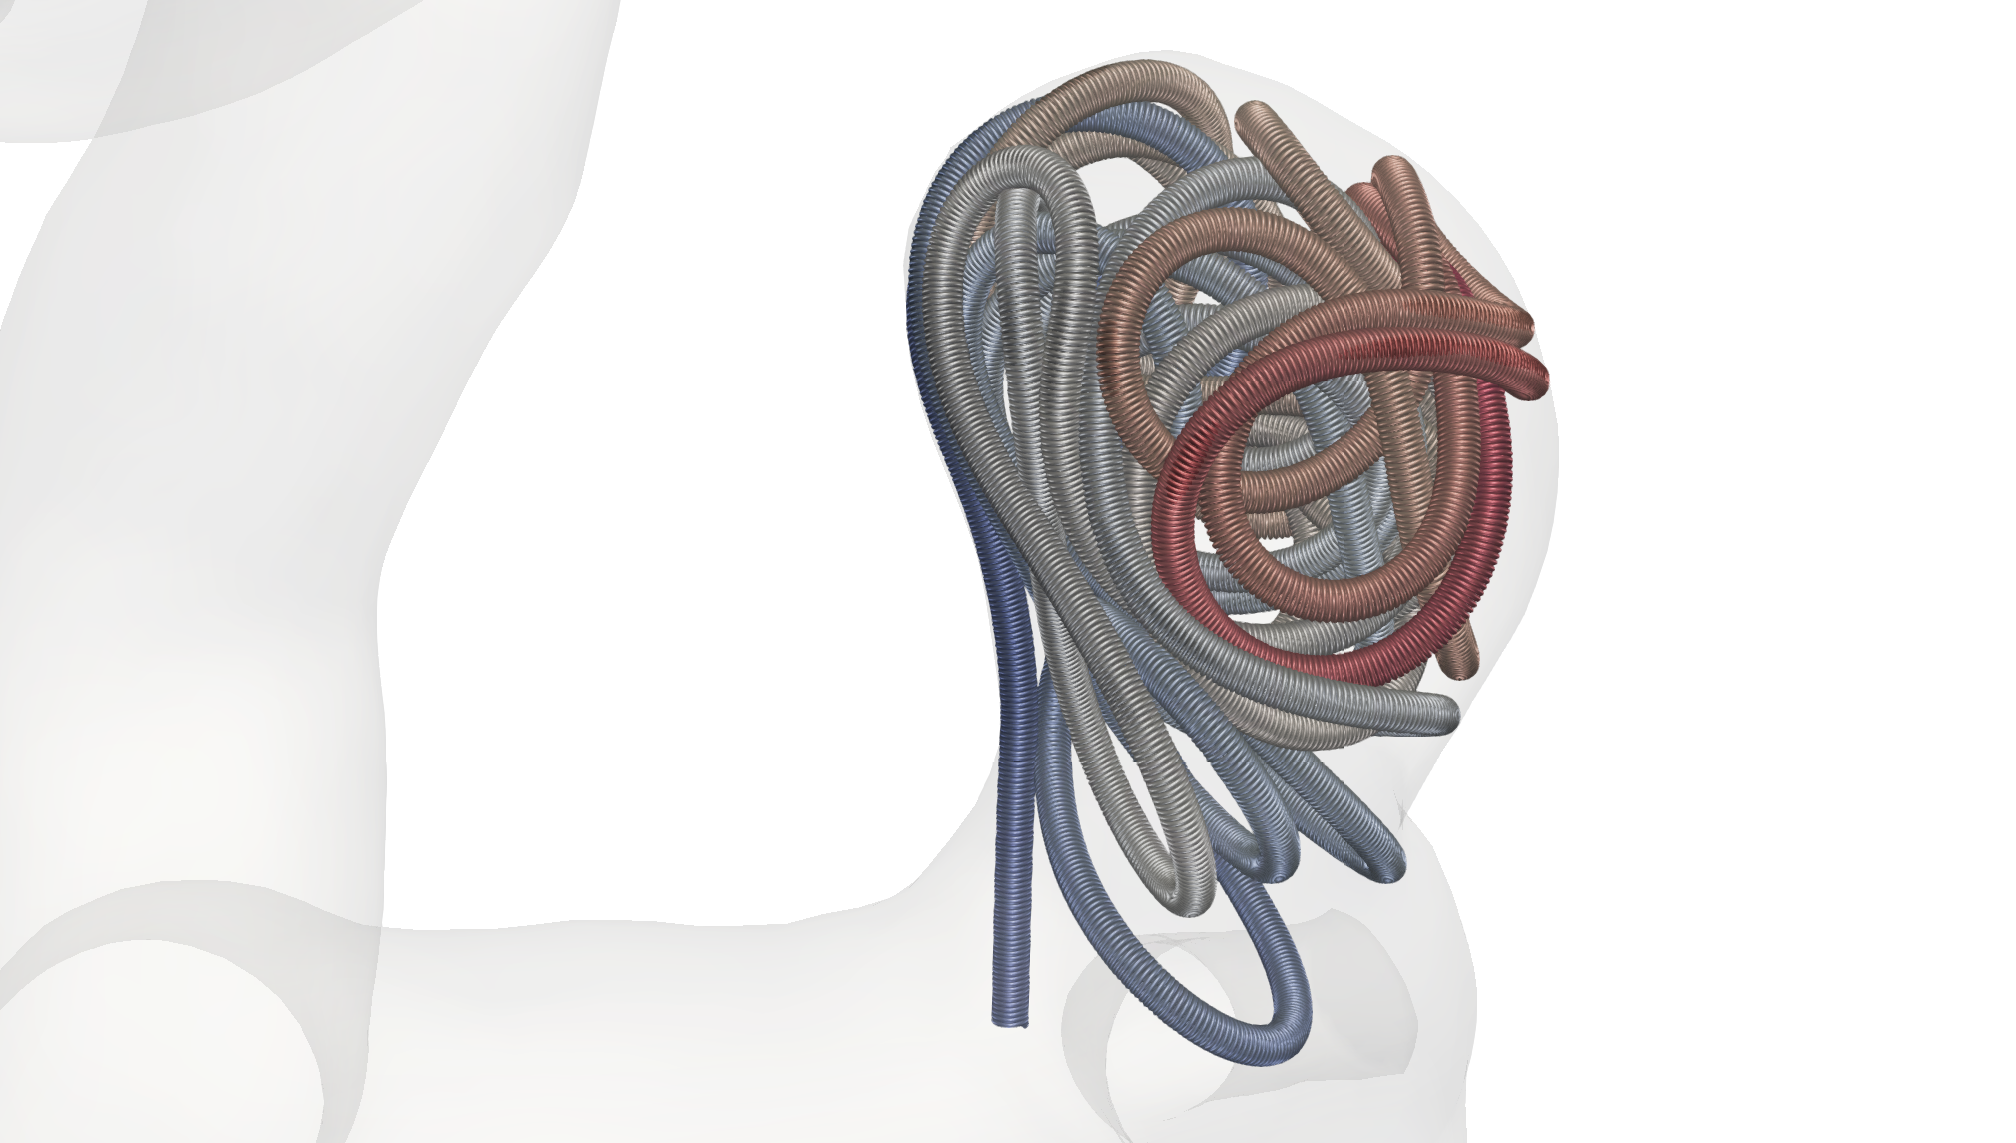

The coiling procedure is conducted under continuous imaging supervision in digital subtraction angiography, a fluoroscopy technique, where an interventionist inserts a catheter through a femoral or radial access to reach for the brain along the upstream of blood, carefully moving to the part where the aneurysm is located. Then, via a micro-catheter, the wire is protruded into the aneurysm dome. Coils do exist in various shapes and sizes as well as with various material properties [23, 27, 51]. A patient-specific choice, e.g., with respect to the length or the imprinted natural shape of the inserted coil(s), is made based on preceding aneurysm measurements as well as the surgeons experience with respect to optimal placement [32]. Possible choices are, e.g., a stiffer framing coil followed by one or several softer filling and finishing coils depending on the shape of the aneurysm, see Fig. 1.

with denoting the coefficients of stick and slip friction, and being the threshold that decides when the model switches between stick and slip friction. All in all, our forces are thereby given as . To conclude this section, we assume that the micro-catheter is modeled as a cylindrical surface without lids following a spline curve that is generated by 3 points in space. By triangulating its surface, we can consider it as rigid object and model its collisions with the coil in the same ways as done in (20). This concludes our discussion of the model we use of the endovascular coil embolization. An example for a embolized coil in the small aneurysm is given in Fig. 8. Here (8(a)), (8(b)) show side views. The view (8(c)) is from bottom, looking through the aneurysm neck into the aneurysm.